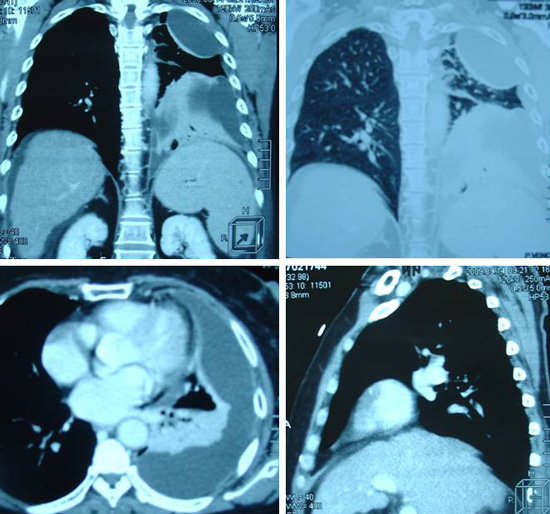

Tidak puas, PC lalu pergi ke sebuah rumah sakit swasta di Ipoh. Pada pemeriksaan X – ray didada kirinya menunjukkan adanya efusi pleura (yaitu adanya cairan di paru-paru kirinya). Cairannya disedot keluar. Sebuah ultrasonagraphy ( dibagian perut ) pada tanggal 23 September 2009 menunjukkan sebuah lesi berukuran 2,6 cm ( diperkirakan hepatoma atau kanker hati) di lobus sebelah kanan. Selain itu, pada organ hatinya sudah terjadi sirosis hati ( mengeras ) dengan hipertensi portal dan adanya ascites ( adanya cairan dibagian perut ). Organ Limpa nya membesar.

Biopsi dari lesi tersebut tidak dapat dilakukan mengingat telah terjadinya ascites, trombosit yang rendah dan keberadaan tumor yang terlalu dalam dan berdekatan dengan vena portal.